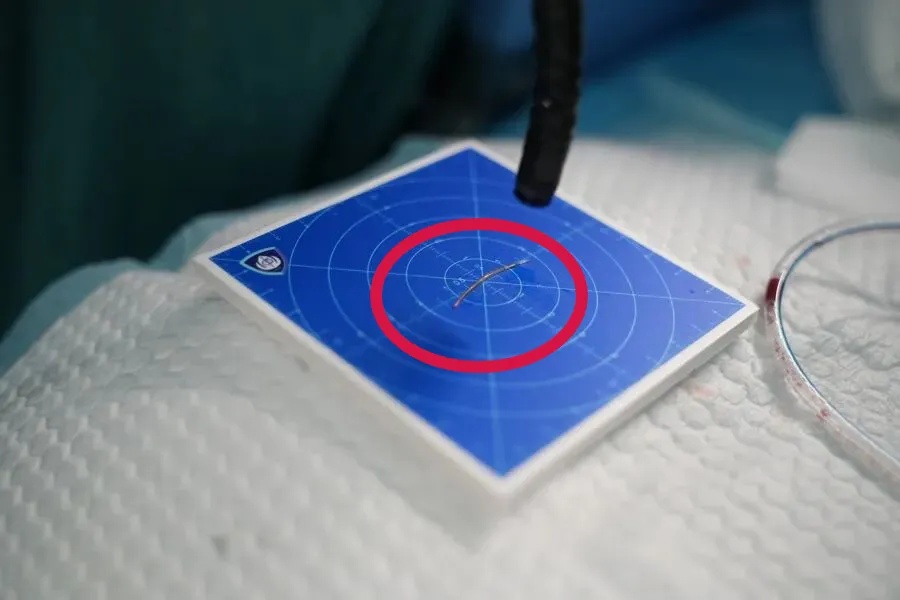

随即,在麻醉科和手术室团队的保障下,张女士被送入手术室。经过细致探查,医生最终在甲状腺左叶上极附近找到并成功取出鱼刺,长度约1.7厘米。随后,手术团队对食管穿孔区域进行规范处理,并清理周围炎性组织,值得一提的是,此次手术仅用了30分钟便顺利完成。